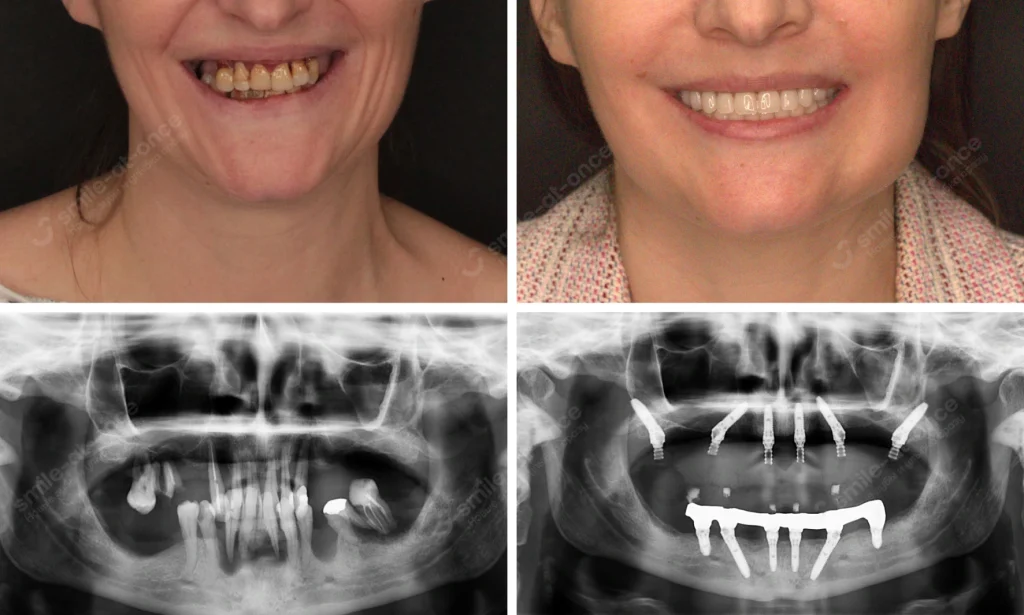

Истории из практики